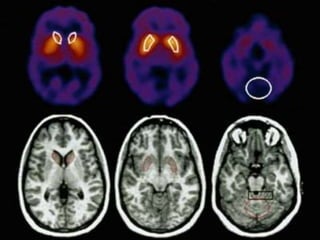

•IMAGINGFOR

PARKINSON’S DISEASE